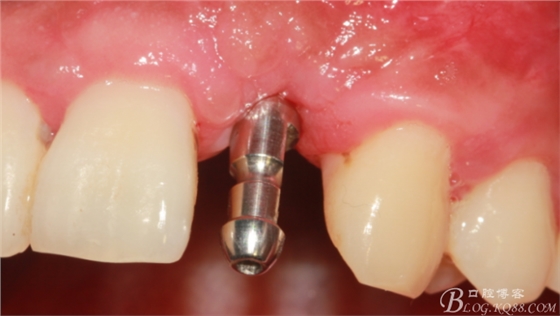

制作臨時(shí)冠。

臨時(shí)冠戴入。